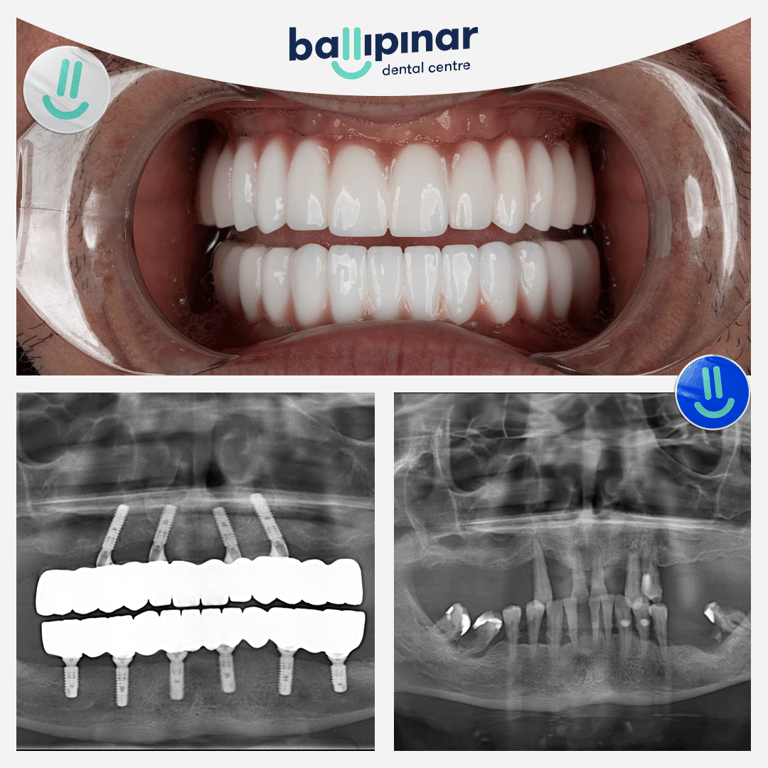

Dental implants Before & After

Explore all the before and after photos of dental implant procedures performed by Ballipinar in Turkey. Contact us today to achieve a beautiful smile.